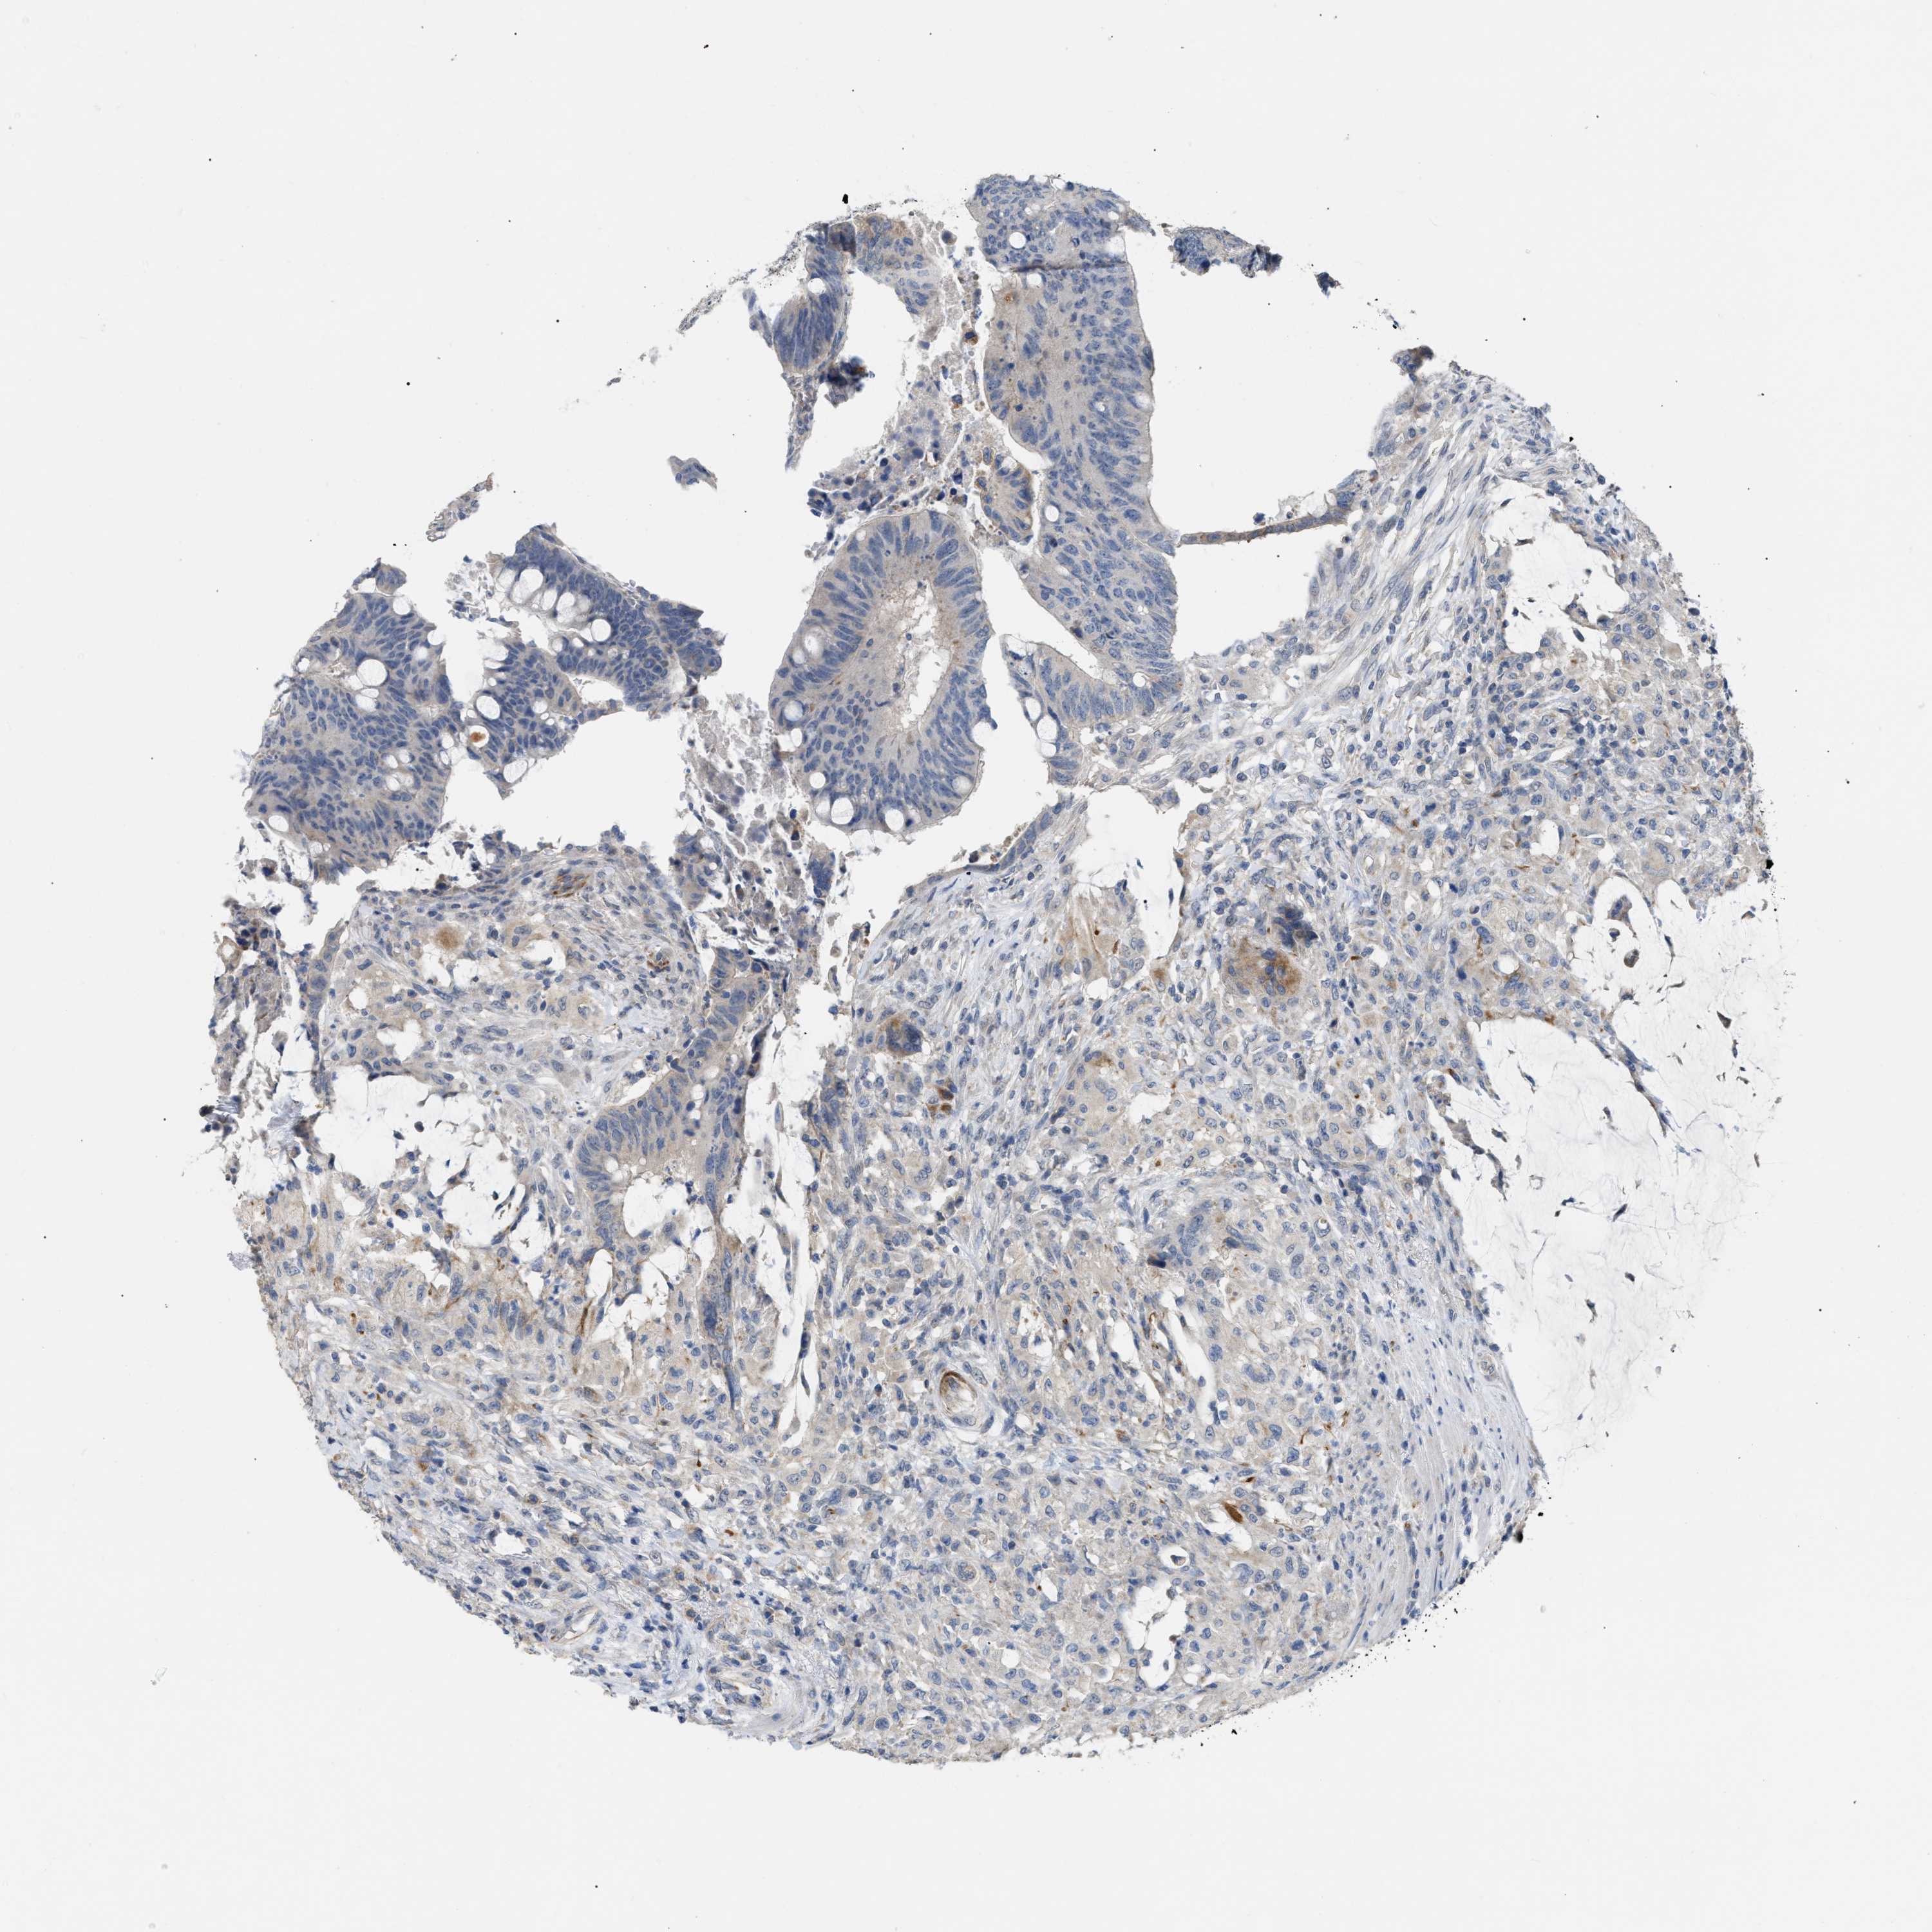

CANCER COLORECTAL CANCER Show tissue menu

Colorectal cancer

Colon adenocarcinoma